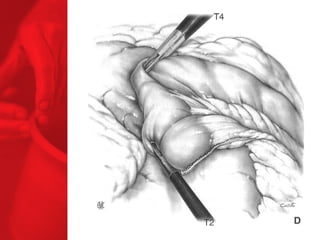

GASTRIC BYPASS Lesprocédures de malabsorption et restrictives > 56% de perte de poids excédentaire après quatre ans* > diminue le diabète de type 2 chez plus de 83 % des patients* *Christou NV, Sampalis JS, Liberman M, et al. Surgery Decreases Long-Term Mortality, Morbidity, and Health Care Use in Morbidly Obese Patients. Annals of Surgery 2004;240(3):416-424. ** Buchwald H, Avidor Y, Braunwald E, et al. Bariatric Surgery—A Systematic Review of the Literature and Meta-analysis. Journal of the American Medical Association 2004 Oct 13;292(14).

Echecs Malgré unebonne technique du CCGL, des échecs surviennent chez 15 à 20 % des patients. Les causes de reprise pondérale sont la dilatation de la poche gastrique, la dilatation de l'anastomose gastrojéjunale, l'hypertrophie des villosités du jéjunum proximal et la prise d'une alimentation avec des liquides à haute teneur en calories. Ainsi, pour les « superobèses » pathologiques (IMC > 50 kg/m2), l'intervention de référence pourrait devenir la diversion biliopancréatique.

COMMENT FONCTIONNE LECOURT-CIRCUIT GASTRIQUE ? Facteurs chirurgicaux Restriction du volume des repas Certaine malabsorption Syndrome de chasse Réduction de l'appétit Facteurs pour les patients Apport en calories Dépense en calories BILAN ENERGETIQUE = apport alimentaire dépense en énergie